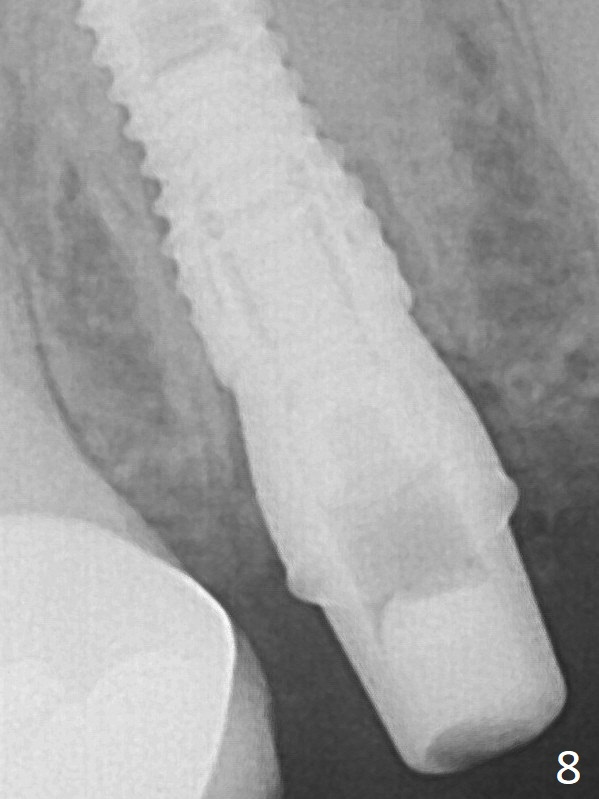

Vanilla graft is placed around the implant (vaguely shown) and a 4.5x4(4) mm abutment is placed immediately for an immediate provisional (Fig.8).